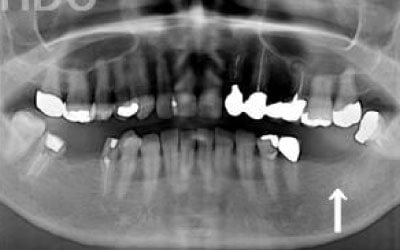

しばらくすると、抜けたままでも慣れてしまうことがありますが、その後に大きな問題が生じることがあります。

1 周囲の歯が早く抜ける

抜けた歯にかかるはずだった噛む力が、知らず知らずのうちに他の歯に負担をかけてしまいます。その結果、残っている歯が突然折れてしまい、抜歯が必要になることがよくあります。

2 歯が傾いてくる、落ちてくる

歯は互いに支え合い、バランスを保っています。そのため、歯が抜けると支えがなくなり、抜けた部分の両隣の歯が傾いたり、上の歯が下に移動してきたりすることがあります。